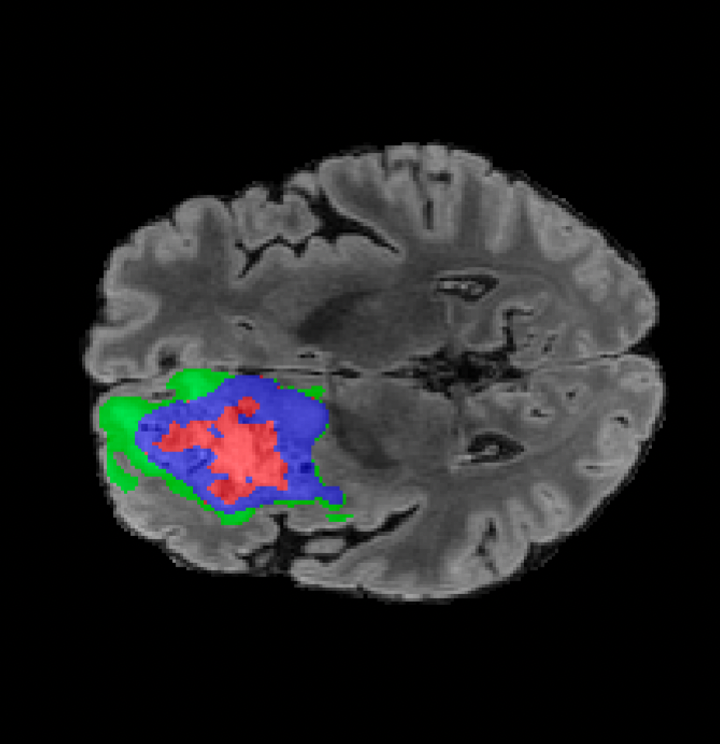

BRATS. The largest public dataset of brain tumours consisting of 5,880 MRI scans from 1,470 brain diffuse glioma patients, and corresponding annotations of tumours[4, 45, 5]. All scans were skull-stripped and resampled to 1 mm isotropic resolution. All images have a resolution of 240 240 155, and we use the flair T2 sequence. Tumours are annotated for 3 classes: Whole Tumour (WT), Tumour Core (TC), and Enhanced Tumour Core (ET).

Tumour Information Preservation. For the brain tumor segmentation, we use a Swin UNETR model[28, 70], trained with random rotation, and intensity as data augmentation. On the test set with human ground-truth annotations (), the brain volumes generated from single slice input preserve the volume of the different tumour components (paired t-test, for all 3 classes). In Figure 4, we highlight the tumor profiles of the generated MRIs compared to the ground truth tumour profile. The real MRI Dice score in the test set is 85.15 while the generated MRIs from a single slice have a dice score of 83.09. This shows how the generated MRIs indeed preserve the tumor information and can act as an affordable and informative pseudo-MRI, before conducting an actual costly MRI examination in hospitals. More detailed results are provided in supplementary material.